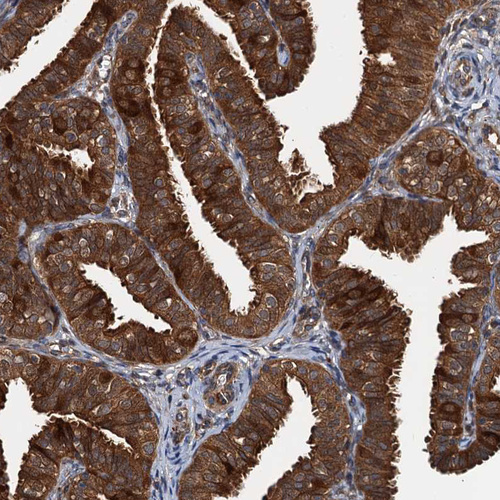

Immunohistochemical staining of human rectum shows strong cytoplasmic positivity in glandular cells.